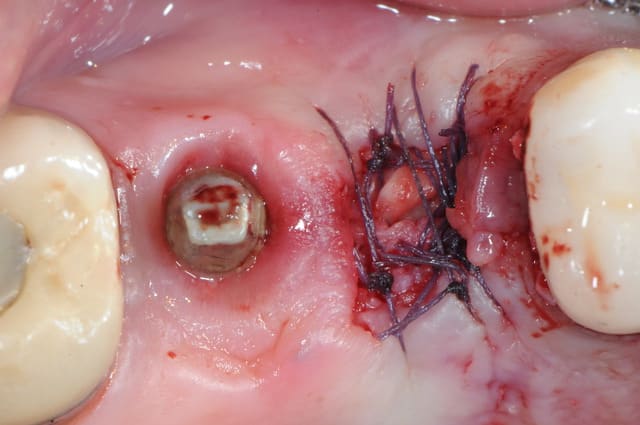

un cas dont j'avais discuté ailleurs avec amibien qui m'avait reproché de ne pas avoir fait la pose en même temps en juin dernier

la pose est de jeudi dernier mon apn est en panne, photo avec le portable, desolé pour le sang mais quand cela saigne il n'y a pas d'échec